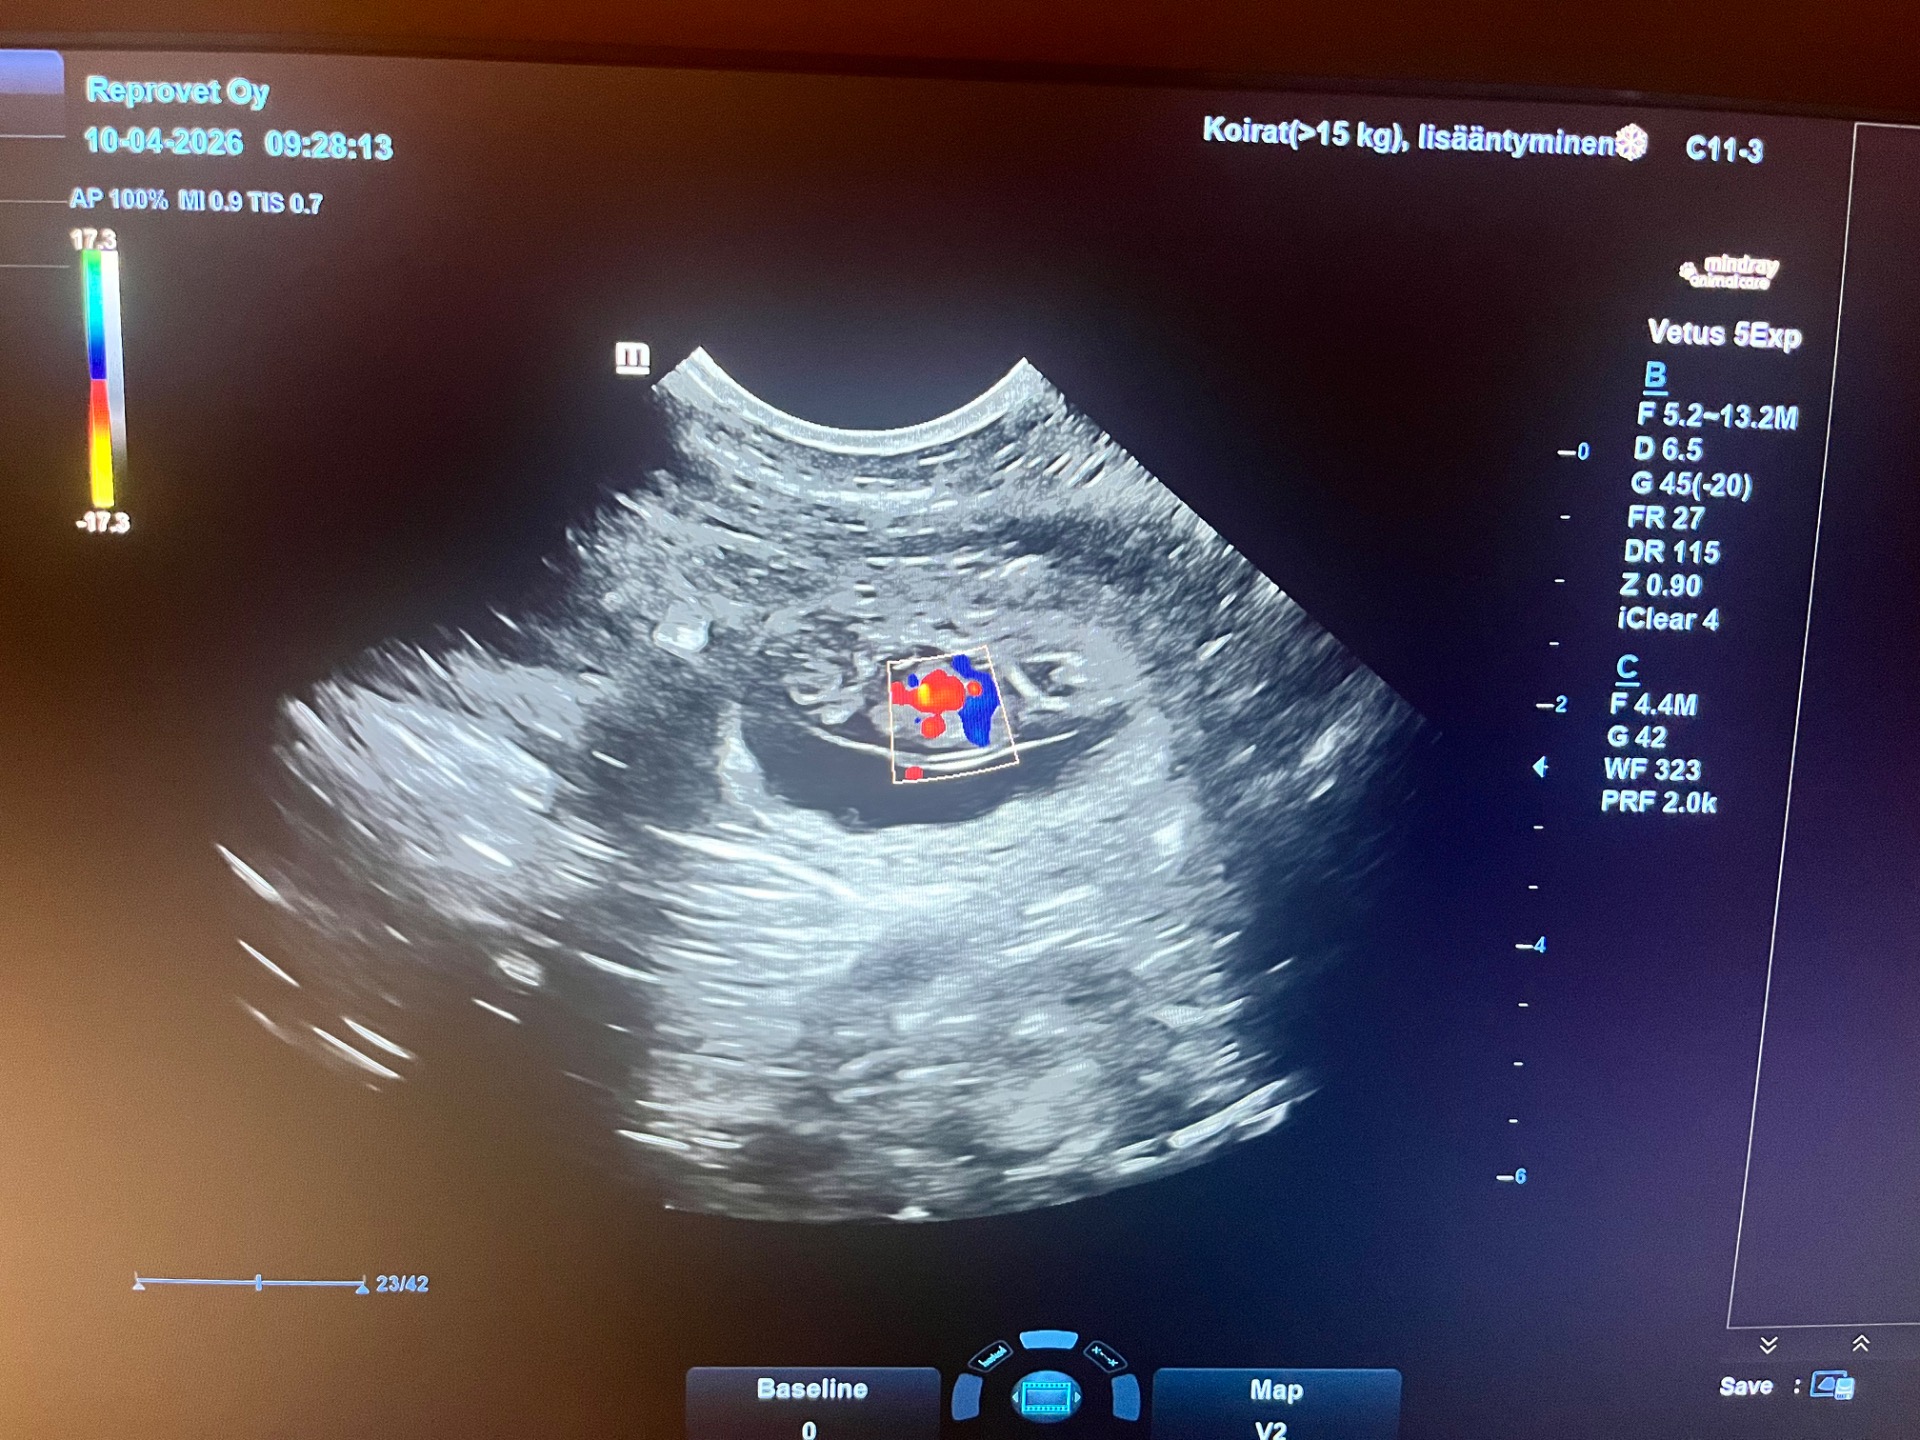

Meiran (Trusted Companion Alina) tiineys varmistui tänään tiineysultrassa, jossa näkyi 8 pikkuista nahkavauvaa. Pennut syntyvät arviolta 12.5.2026. Pentujen isä on Dazzly (Millake’s Dazzling Broderick).

10.4.2026 tiineysultra